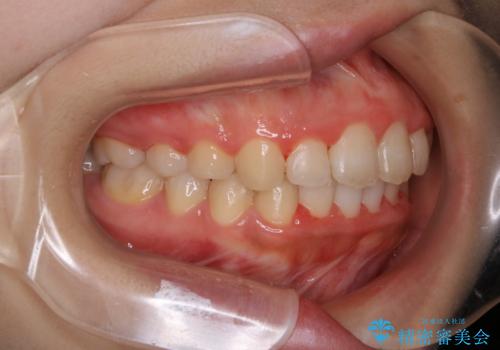

- 20代女性

- ワイヤー審美装置

- 7ヶ月

- 4年ほど前から地元の歯科医院にてインビザライン治療を行っていたが、引っ越し後に通いづらくなってしまったため、治療が途中で止まってしまっているとの事で来院されました。性格的にインビザラインの継続した使用が難しいとのことで、ワイヤー装置にて最終仕上げを行いました。

インビザラインは20時間以上の装着を厳守して頂くことで治療効果が期待できる治療となります。固定式のワイヤー装置に切り替えることで短期間で歯並びを整えることができ、大変喜んでいただけました。